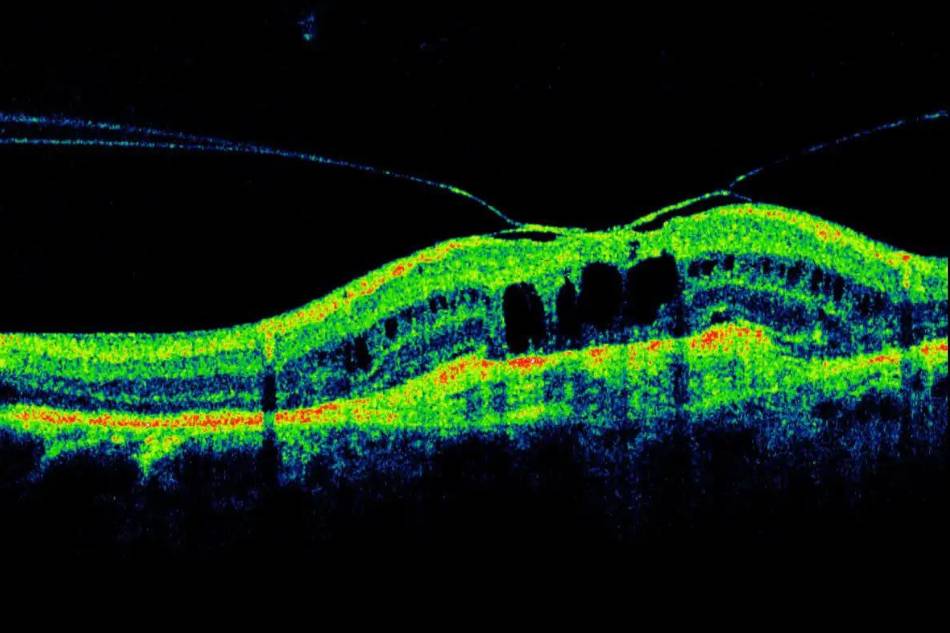

L’OCT per una visita oculistica più approfondita

Effettuare periodicamente una visita oculistica completa è importante per assicurarsi di essere in buone condizioni di salute.